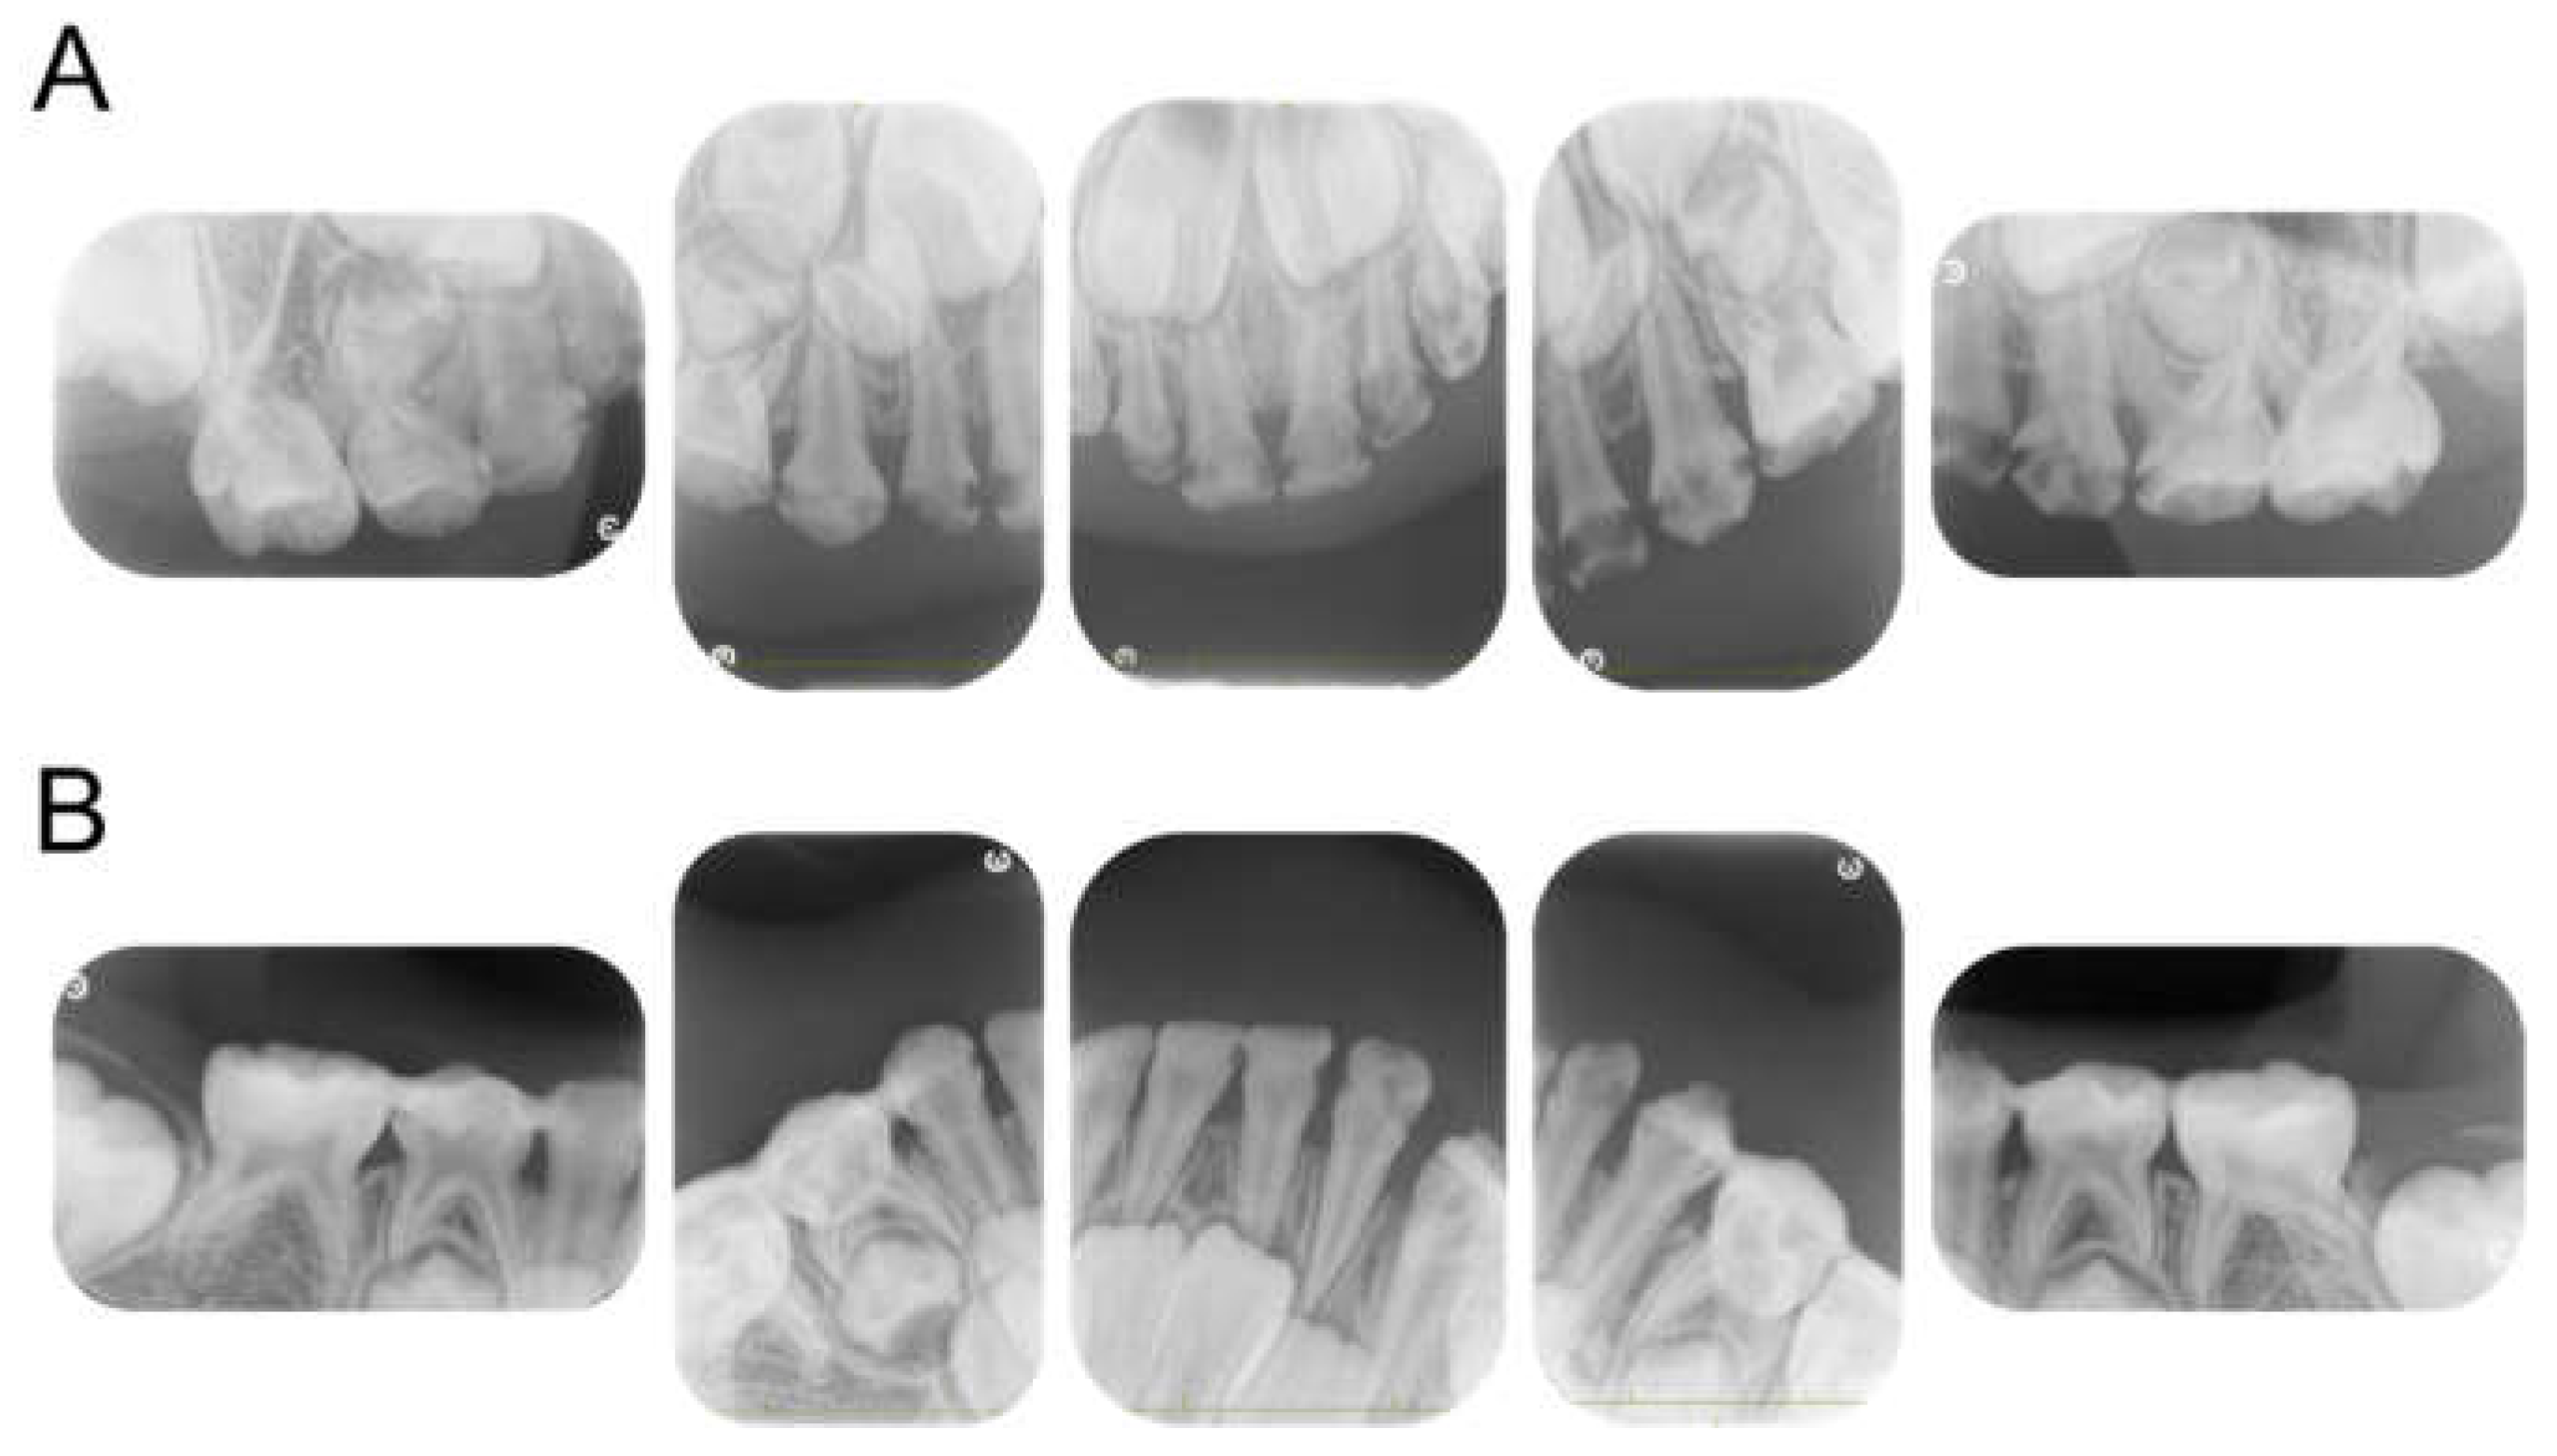

| Tooth | Diagnosis | Final Restoration |

|---|---|---|

| Maxilla | ||

| 51 | C2 | Resin-based composite crown |

| 52 | C2 | Resin-based composite crown |

| 53 | C2 | Resin filling |

| 54 | C2 | Preformed stainless-steel crown |

| 55 | C2 | Preformed stainless-steel crown |

| 61 | C2 | Resin-based composite crown |

| 62 | C2 | Resin-based composite crown |

| 63 | C2 | Resin filling |

| 64 | C2 | Preformed stainless-steel crown |

| 65 | C2 | Preformed stainless-steel crown |

| Mandible | ||

| 71 | C2 | No treatment |

| 72 | C2 | Resin filling |

| 73 | C2 | Resin filling |

| 74 | C2 | Preformed stainless-steel crown |

| 75 | C2 | Preformed stainless-steel crown |

| 81 | C2 | No treatment |

| 82 | C2 | Resin filling |

| 83 | C2 | Resin filling |

| 84 | C2 | Preformed stainless-steel crown |

| 85 | C2 | Preformed stainless-steel crown |